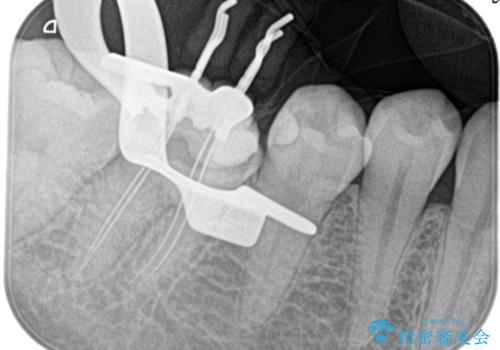

- 奥歯がズキズキ痛いことを主訴に来院されました。

検査の結果、診断を症候性不可逆性歯髄炎、症候性根尖性歯周炎とし抜髄を行っております

根管充填はhydraulic condensation techniqueにて行なっております。

シーラーはWell pulp ST 使用